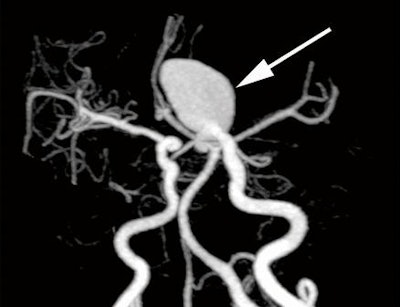

Volume-rendered image (above) and maximum-intensity-projection image (below) from a 47-year-old woman with a left internal carotid aneurysm (arrows). Images courtesy of Radiology.

Nonsubtracted volumetric CTA had a comparable diagnostic ability to subtracted volumetric CTA and 3D DSA for detecting aneurysms of the anterior communicating artery, the posterior communicating artery, the anterior cerebral artery, and the middle cerebral artery, the researchers found.

"The aneurysms missed at nonsubtracted volumetric CT angiography were generally located in the internal carotid artery," they wrote. "Detection of cerebral aneurysms adjacent to bone tissue was still challenging at nonsubtracted volumetric CT angiography because of the presence of overlying bone structures."